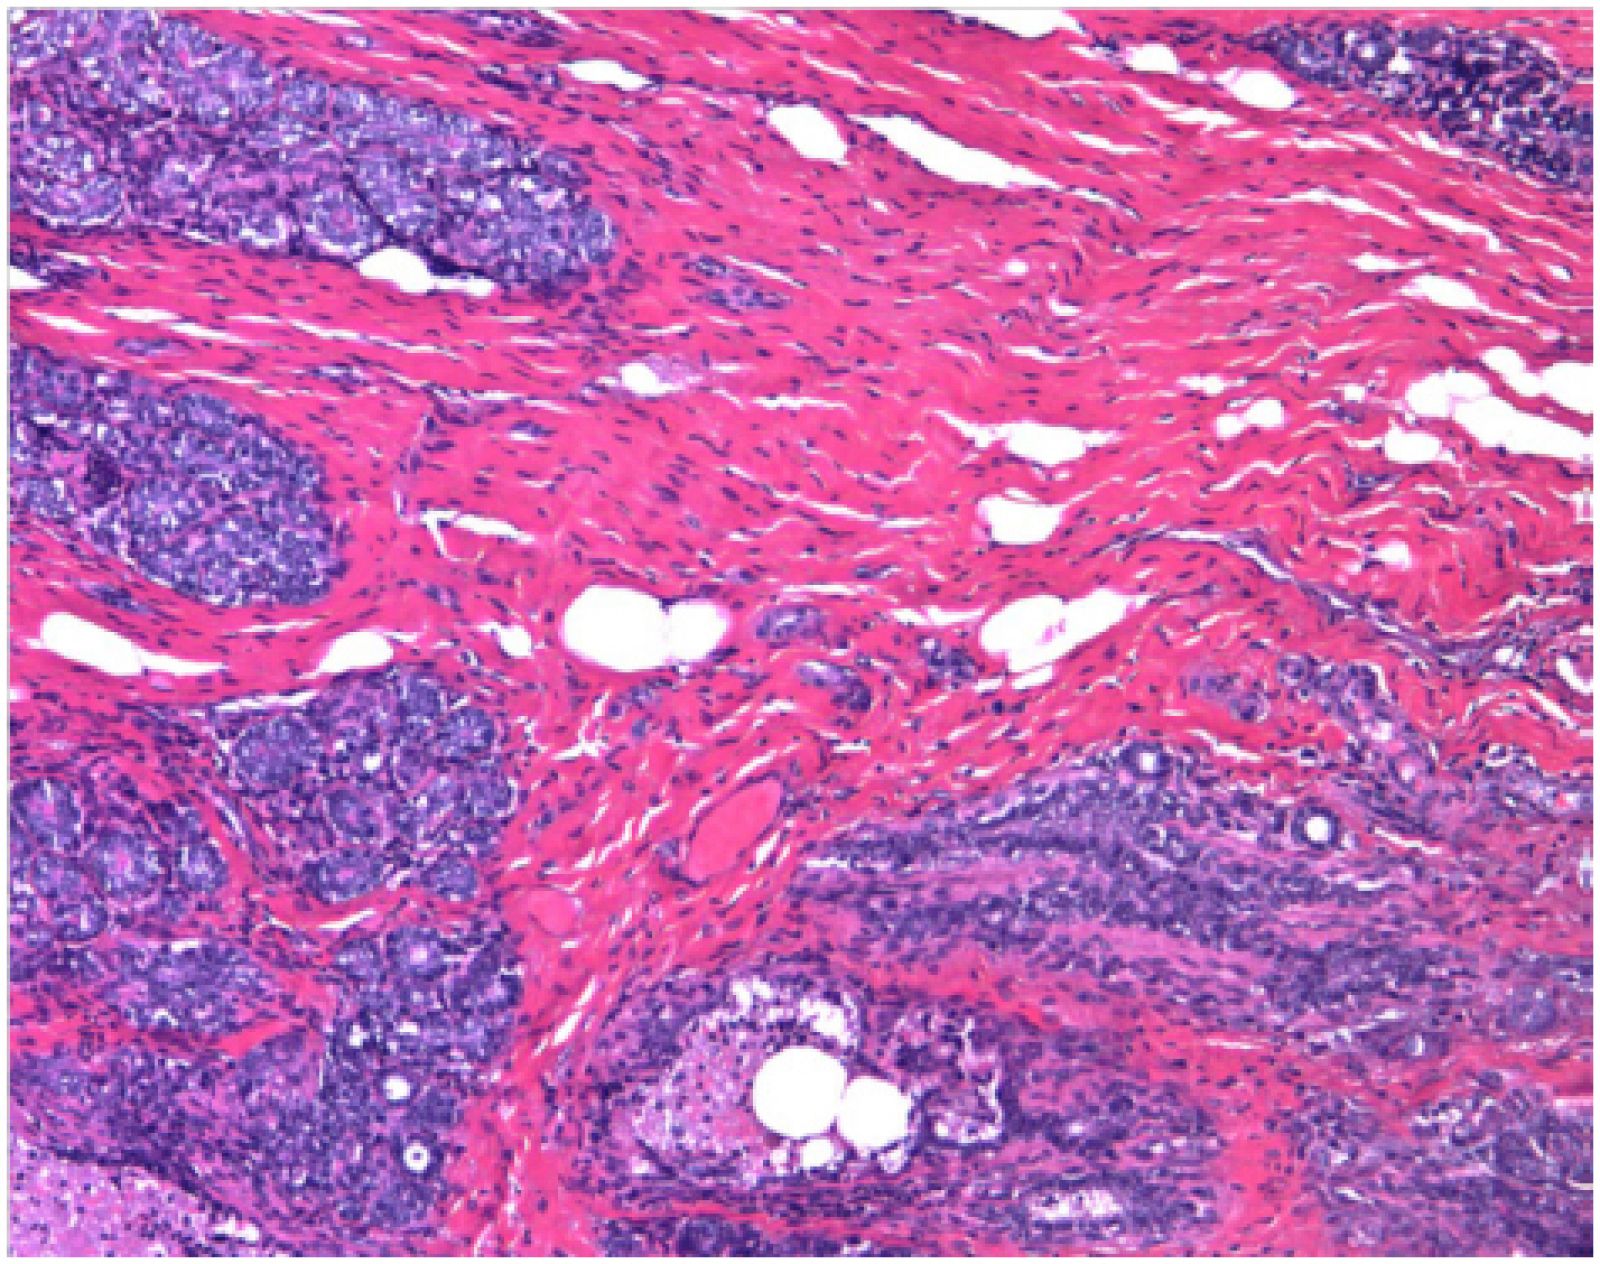

Imagen de un tumor de mama identificado como Epi-Luminal B de pronóstico complicado.

"Uno que hemos llamado Epi-Basal, caracterizado por la pérdida de marcas epigenéticas que causa roturas en los cromosomas, y otro que hemos llamado Epi-Luminal B, definido para presentar inactivación epigenética de genes importantes que deberían proteger del cáncer y en estas células alteradas ya no pueden hacerlo", según ha indicado Esteller.

Según señala el investigador lo más destacado del hallazgo es que el subtipo Epi-Luminal B se comporta de forma especialmente agresiva, y está asociado a una supervivencia menor de las pacientes.